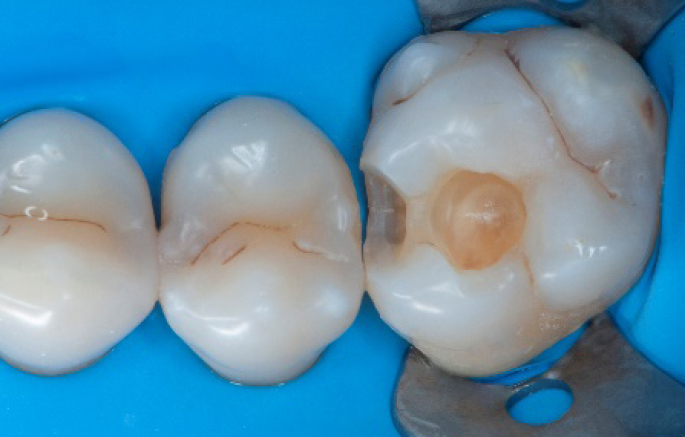

Initial situation of the patient

The patient came for a routine control appointment. She didn‘t report any symptoms but some bleeding during brushing.

Initial situation: an old class I composite restoration on 1.6. New caries on the mesial wall. Presence of plaque and inflammation.

• On the x-ray examination, a mesial translucency (initial caries) was found on tooth 1.6.

• The tooth presented an old class I composite restoration.

• Marginal inflammation and plaque were present.

• No symptoms were referred by the patient.